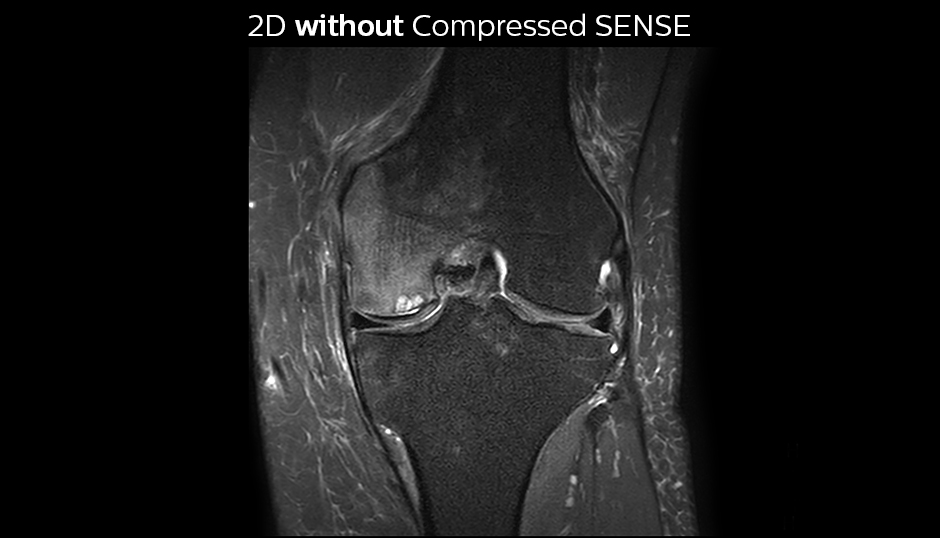

Comparing 2D with 3D using Compressed SENSE

A good acquisition time with high resolution is obtained when moving from three 2D acquisitions in three planes to one 3D acquisition with Compressed SENSE. In this example, Compressed SENSE with 3D VIEW PD SPAIR is 50% faster than three separate 2D scans and has improved spatial resolution.

Without Compressed SENSE

Three separate 2D PD scans in three orientations

Scan time 2:55 + 3:37 + 3:51 = 10:23 min.

Voxel size 0.55 x 0.65 x 3 mm

PD FS SPIR knee WITHOUT Compressed SENSE sag

Compressed sense C3

PD FS SPAIR knee without Compressed SENSE cor

With Compressed SENSE factor 10

3D VIEW PD SPAIR high resolution knee

Scan time 5:03 min.

Voxel size 0.6 x 0.6 x 0.6 mm

3DVIEW PD SPAIR knee Compressed SENSE factor10 sag

PD mDIXON water knee WITHOUT Compressed SENSE tra

3DVIEW PD SPAIR knee Compressed SENSE factor10 mprcor